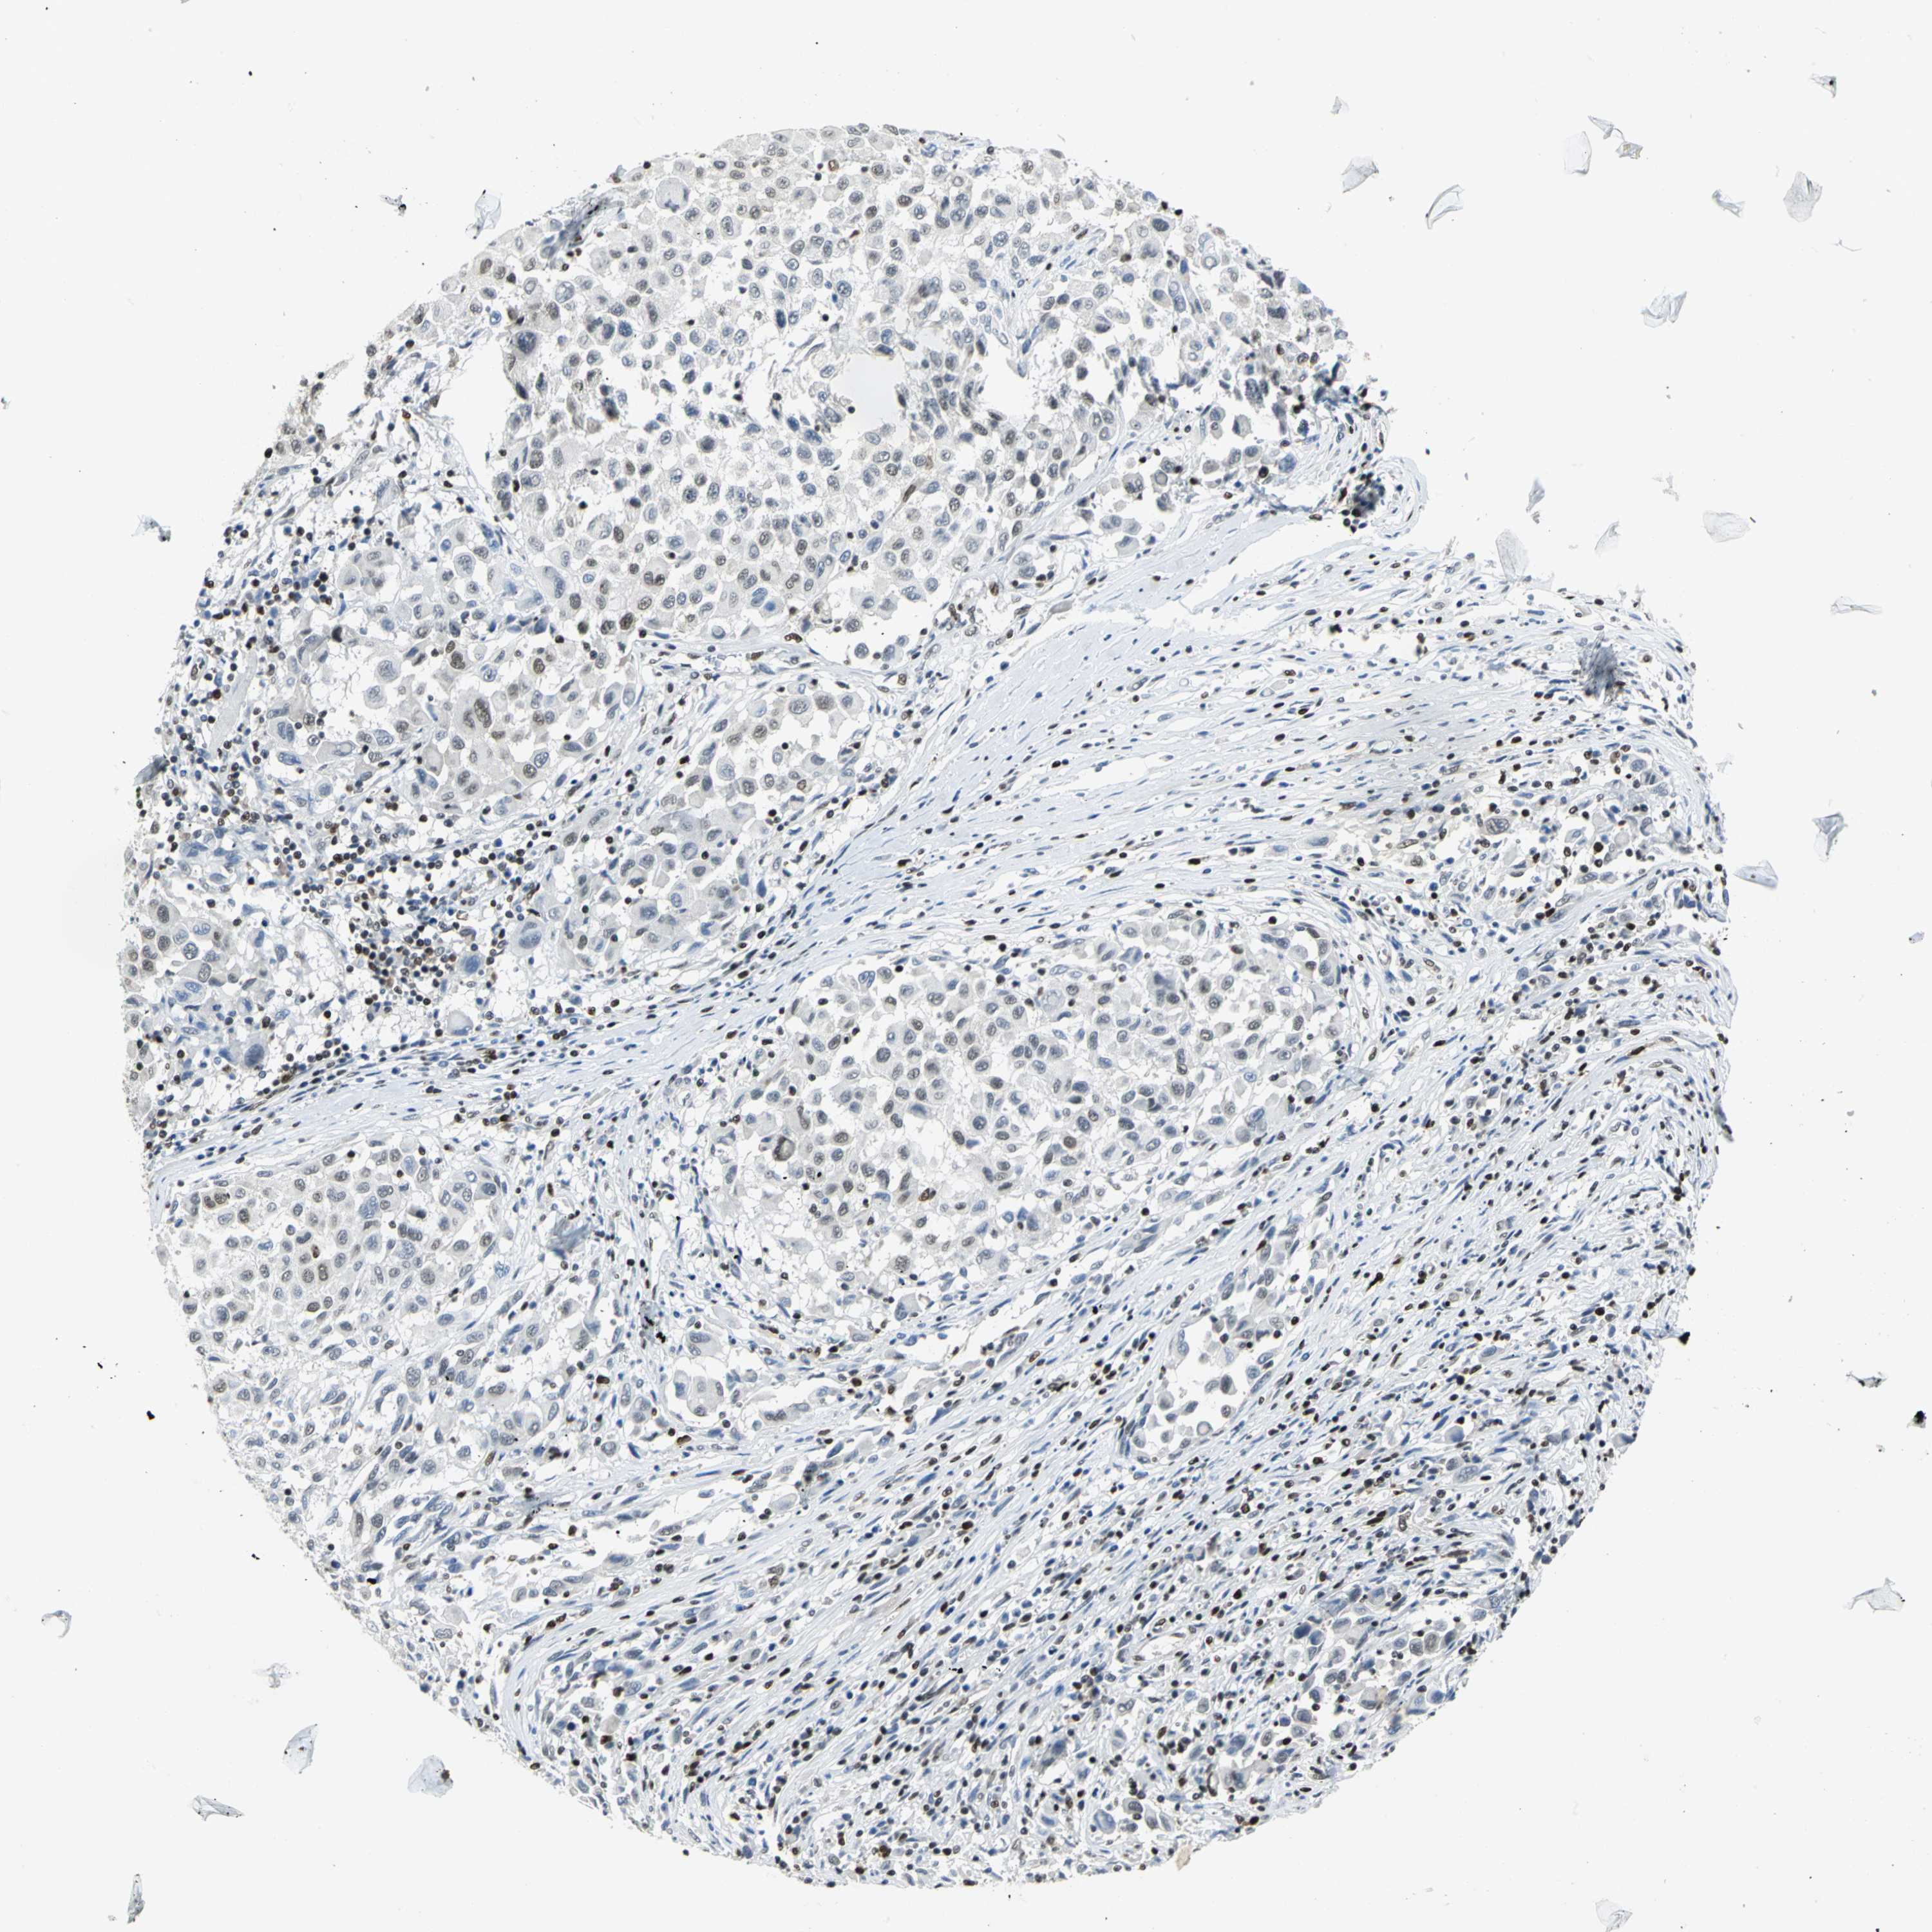

MELANOMA - Protein expressioni

A mouse-over function shows sample information and annotation data. Click on an image to view it in a full screen mode. Samples can be filtered based on level of antibody staining by selecting one or several of the following categories: high, medium, low and not detected. The assay and annotation is described here.

Note that samples used for immunohistochemistry by the Human Protein Atlas do not correspond to samples in the TCGA dataset.

Antibody stainingi

Antibody staining in the annotated cell types in the current human tissue is reported as not detected, low, medium, or high, based on conventional immunohistochemistry profiling in selected tissues. This score is based on the combination of the staining intensity and fraction of stained cells.

Each image is clickable and will lead to virtual microscopy that enables deeper exploration of all samples and also displays staining intensity scores, fraction scores and subcellular localization as well as patient and tissue information for each sample.

Antibody HPA004911

Staining

High

Medium

Low

Not detected

Intensity

Strong

Moderate

Weak

Negative

Quantity

>75%

75%-25%

<25%

None

Location

Nuclear

Cytoplasmic/membranous

Cytoplasmic/membranous,nuclear

Malignant melanoma, NOS

Malignant melanoma, Metastatic site